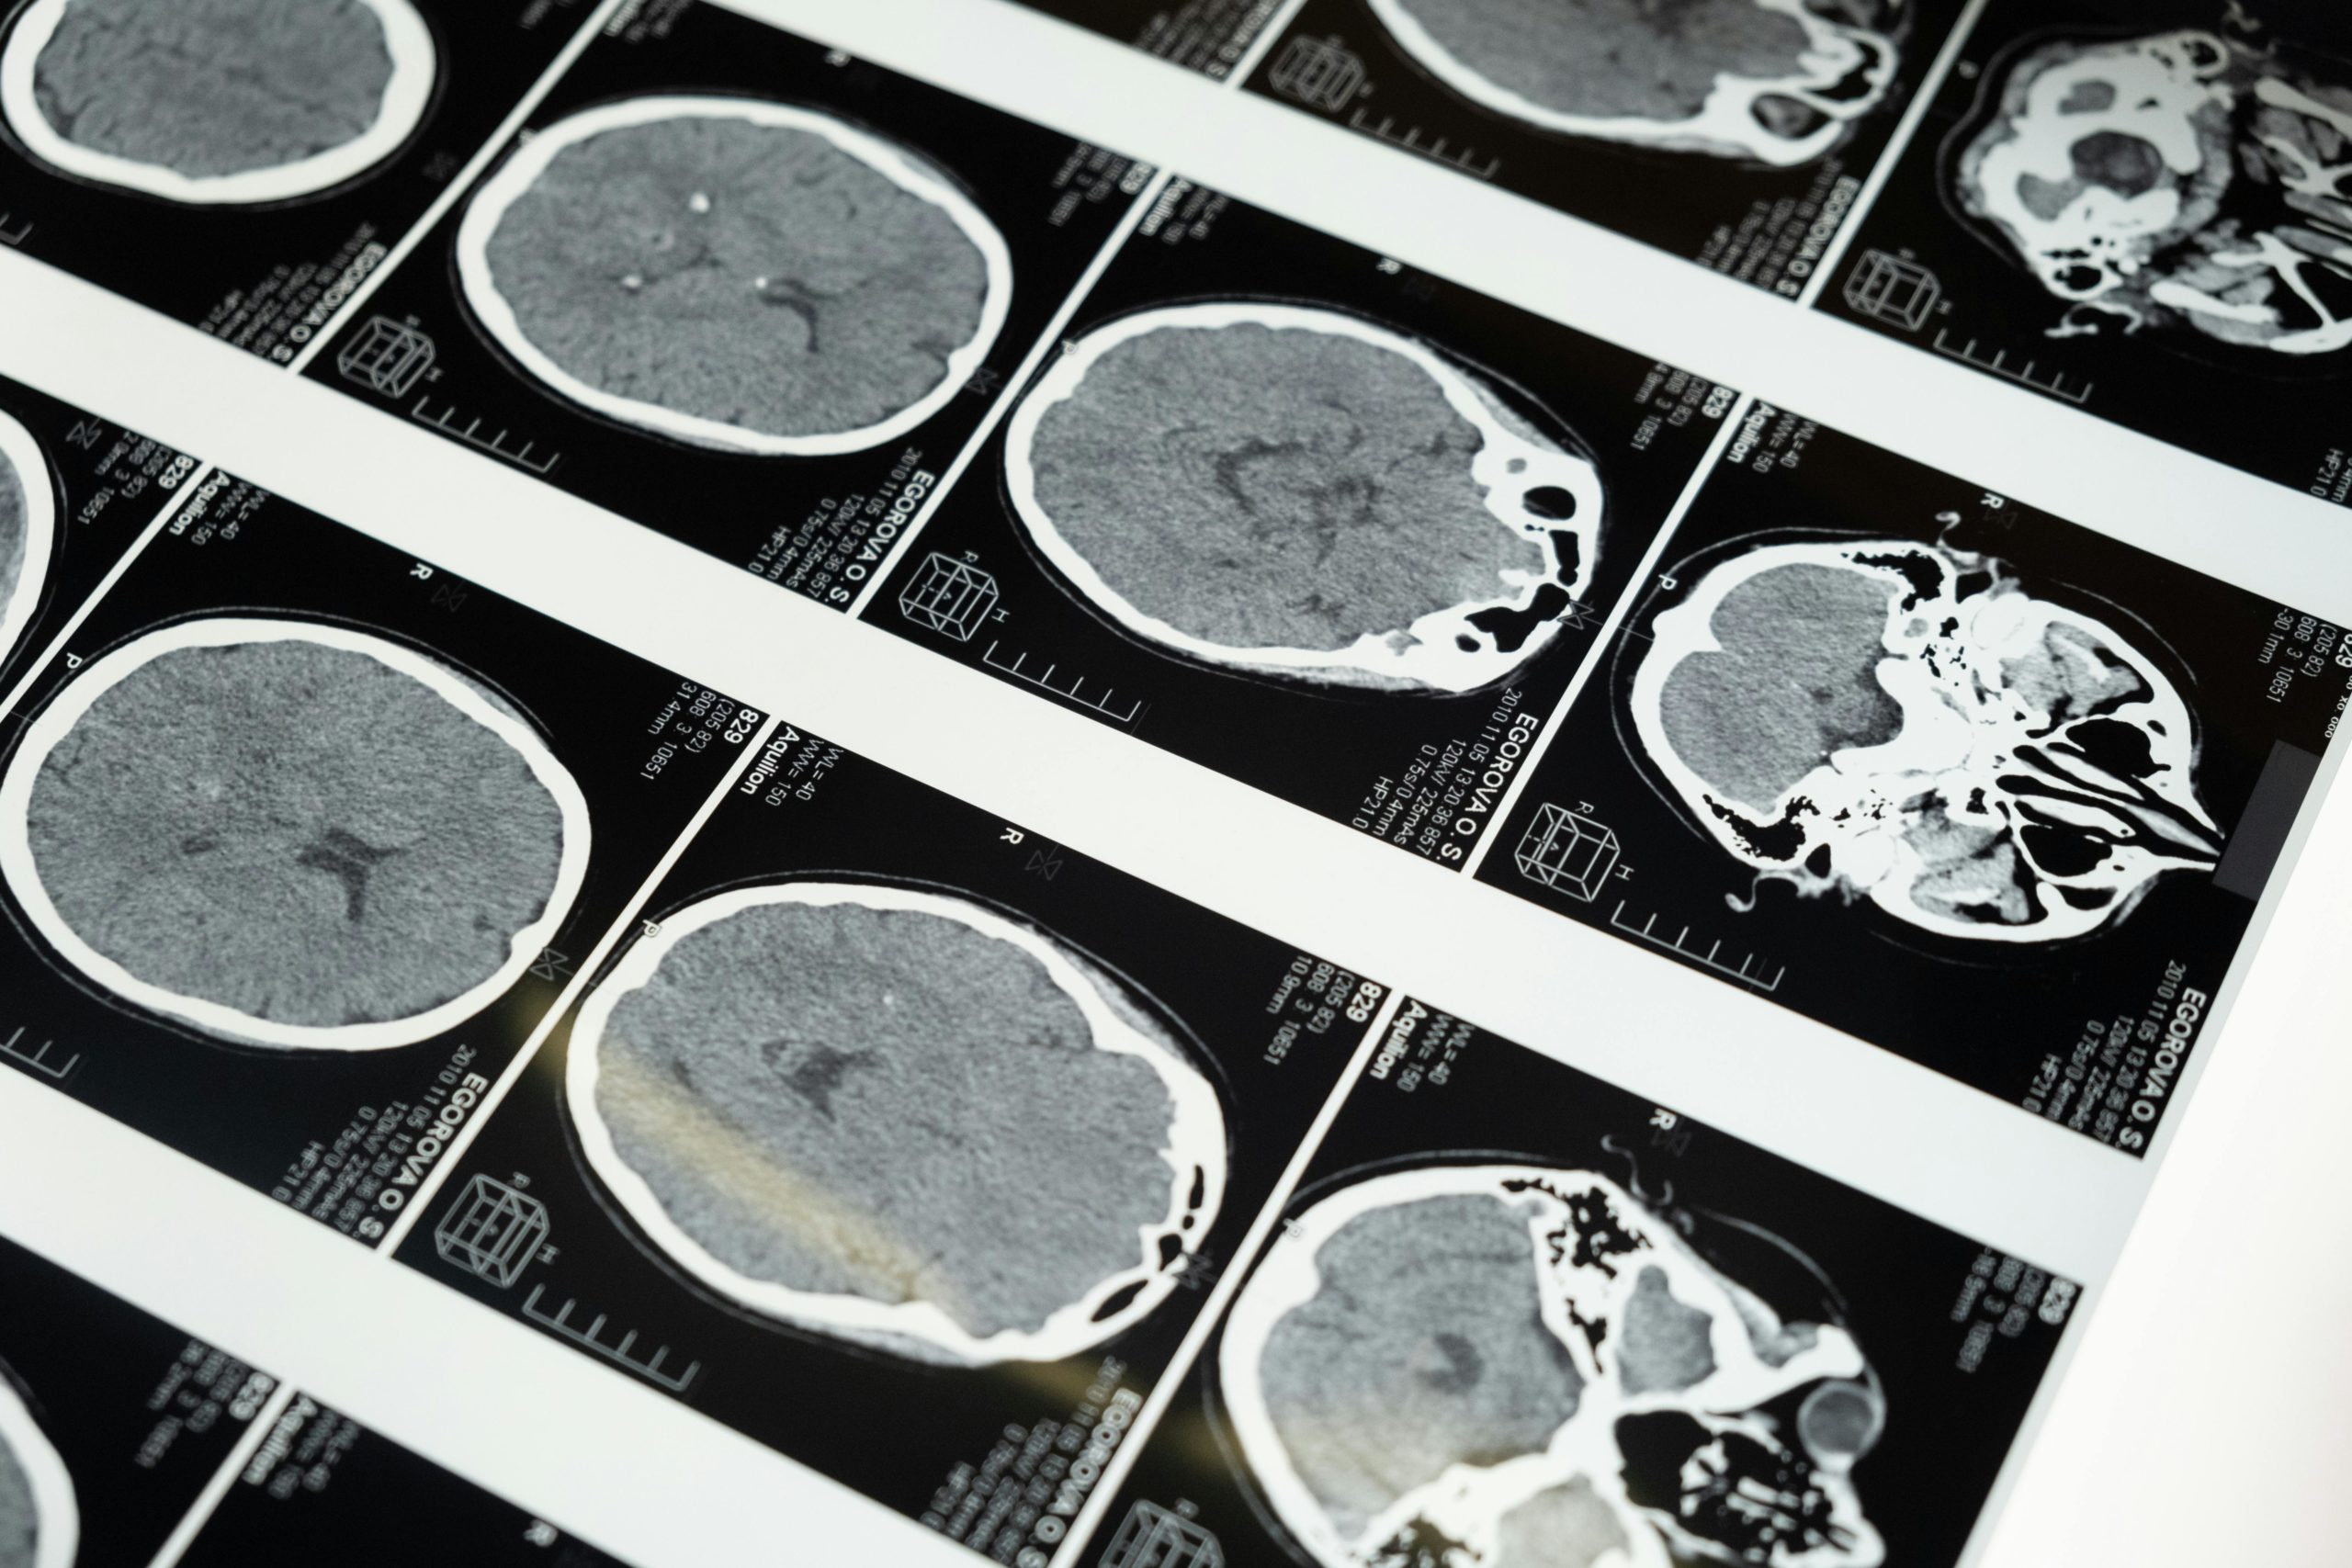

Gehirnforscher nutzen verschiedene Methoden, um im lebenden Menschen Einsicht in die Hirnaktivität zu gewinnen. Die wichtigsten Verfahren sind bildgebende Neuroimaging-Methoden und das EEG.

• MRT (Magnetresonanztomografie): Mit dem MRT können Forscher die Struktur und teilweise auch die Aktivität des Gehirns messen. Normale MRT-Bilder zeigen z. B. das Volumen von Hirnarealen oder bestimmen, ob die Anatomie normal ist. In der Lernforschung verwendet man vor allem das fMRT (funktionelle MRT). Dabei bleibt die Person in einer Röhre liegen und löst Aufgaben, während das Gerät Blutfluss und Sauerstoffverbrauch misst. Aktive Hirnregionen „leuchten“ dadurch in den Bildern auf.

• PET (Positronen-Emissions-Tomografie): Hierfür injiziert man eine schwach radioaktive Substanz, die sich im Blut verteilt und vor allem in besonders aktiven Hirnarealen anreichert. Die Messung zeigt dann eine Art „Karte“ der Gehirnaktivität. Ein Vorteil ist, dass bestimmte Stoffwechselvorgänge sichtbar werden. Allerdings ist PET aufwendiger und kommt seltener in der Lernforschung zum Einsatz.

• EEG (Elektroenzephalographie): Das EEG misst elektrische Hirnströme über aufgeklebte Elektroden auf der Kopfhaut. Es hat eine sehr hohe zeitliche Auflösung, so dass man nahezu in Echtzeit verfolgen kann, wie Neuronen auf Reize reagieren. Allerdings ist die räumliche Auflösung schlechter – man sieht zwar Wellenmuster, kann aber nur grob sagen, aus welchem Hirnareal sie stammen. In Lern Experimenten ist das EEG deshalb vor allem nützlich, um z. B. Aufmerksamkeitsschwankungen, Gehirn-Rhythmen oder Gedächtnisprozesse mit hoher Genauigkeit zu erfassen.